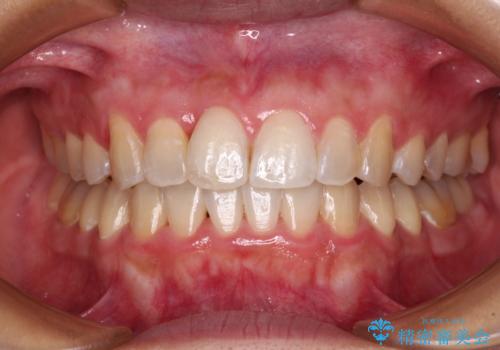

前歯のデコボコをインビザラインでスッキリと仕上げる

- 上下前歯のデコボコと奥歯の銀歯を気にして来院された患者様です。

口元をインビザラインにより歯列を整え、その後に失活している奥歯をオールセラミッククラウンにて補綴治療することとしました。

長時間のマウスピース装着に協力いただき、自然な口元に仕上げることができました。

気になっていた銀歯もオールセラミッククラウンで本物の歯のようになり、患者様には大変満足していただきました。